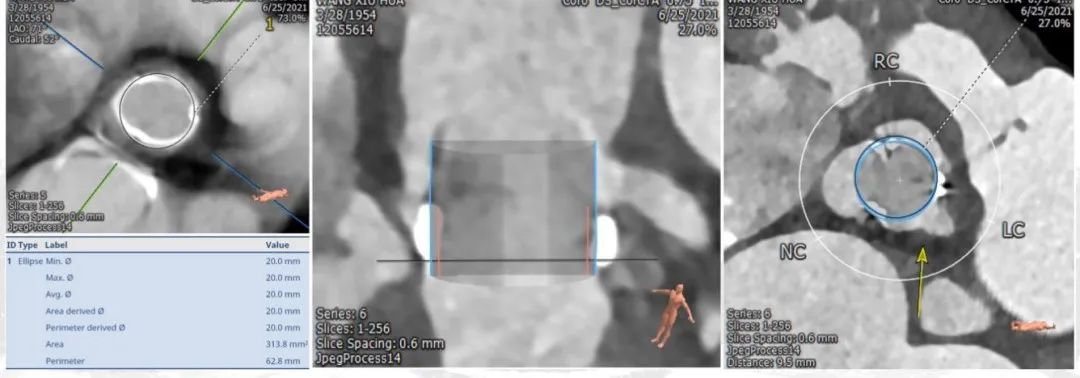

(一)主动脉瓣位评估:

左心耳无血栓,perimount 21瓣膜瓣环,左室流出道,窦管交接区,升主动脉评估,心室大小,全主动脉入路评估,冠脉风险评估,详细见下图。

1. 基本层面CT评估(图1)

4. 主动脉瓣膜模植入与冠脉风险评估(图4)

拟植入20型号与23型号比较,20型号的SAPIEN 3瓣膜植入冠脉闭塞影响小

5. SAPIEN 3瓣膜尺寸图(图5)